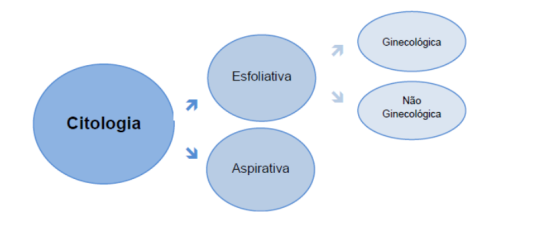

Citopatologia

Estudo da patologia ao nível celular, ou seja, as alterações induzidas por processos patológicos.

Citologia Esfoliativa – Análise de células descamadas (esfoliadas), obtidas a partir de superfícies anatómicas (naturalmente ou com auxílio de meios técnicos).

- Ginecológica – Exame de rastreio do cancro do colo do útero, também conhecido como teste de Papanicolaou. Pode ser efectuado em lâminas (esfregaços) ou em meio líquido. Em ambos, a colheita é realizada da mesma forma. Posteriormente, é elaborado um relatório segundo o Sistema de Bethesda.

- Não Ginecológica – Exame que inclui a análise de amostras do aparelho respiratório (escovado brônquico, lavado broncoalveolar, secreção brônquica); líquidos de cavidades serosas (ascítico, pericárdico e pleural); urina e líquido cefalorraquidiano, entre outras.

Citologia Aspirativa por Agulha Fina (CAAF) – Exame rápido e pouco invasivo, no qual, através da aspiração, se obtém material para diagnóstico citológico. Pode ser utilizado em lesões palpáveis e não palpáveis (nestas últimas com recurso a controlo imagiológico).